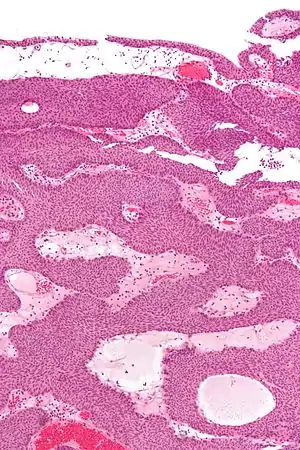

| Micrograph of an inverted papilloma of the urinary bladder. H&E stain. | |

.jpg.webp) Histopathology representing an inverted papilloma of the urinary bladder that was cystoscopically resected. Hematoxylin and eosion stain.

Histopathology representing an inverted papilloma of the urinary bladder that was cystoscopically resected. Hematoxylin and eosion stain..jpg.webp) Histopathology representing an inverted papilloma of the urinary bladder that was cystoscopically resected. Hematoxylin and eosion stain.

Histopathology representing an inverted papilloma of the urinary bladder that was cystoscopically resected. Hematoxylin and eosion stain..jpg.webp) Histopathology representing an inverted papilloma of the urinary bladder that was cystoscopically resected. Hematoxylin and eosion stain.